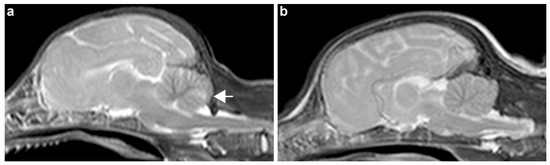

3.1. Clinical Description

3.2. Necropsy and Histopathological Examinations